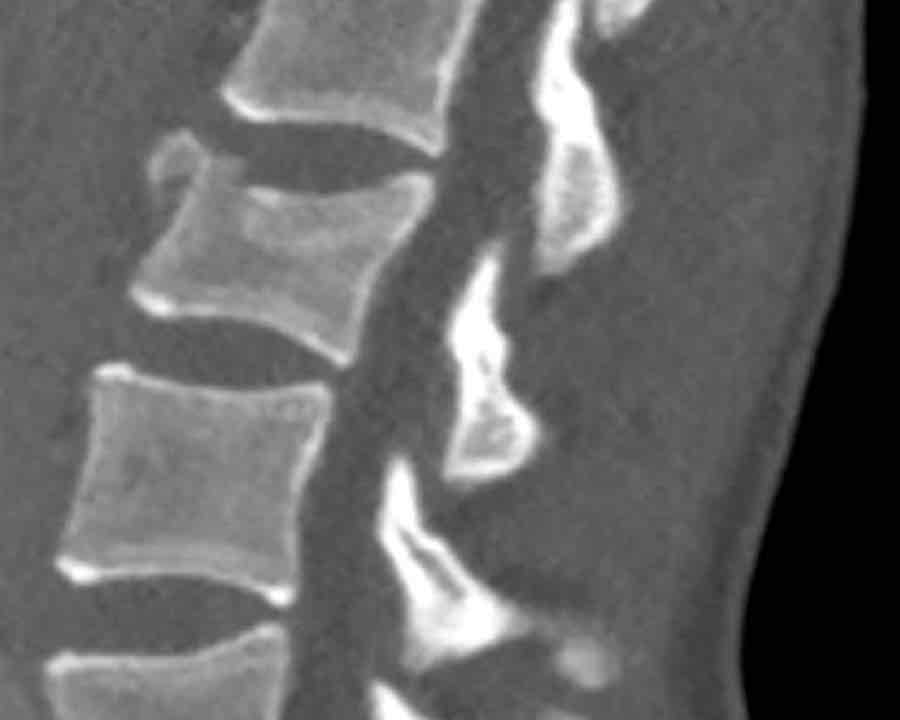

Findings

- Clear widening of the interspinous distance (yellow arrow)

- Black arrowhead: small avulsion fracture to the flexion distraction

- MRI better depicts the ligamentous injury, which was suspected on CT

Conclusion

Injury type B2

- Subtle widening of the interspinous distance (white circle)

- Small avulsion fracture spinous process (yellow arrow)

- Compression fracture with involvement of one endplate and posterior wall (1+2 points)

Injury type B2 + A3